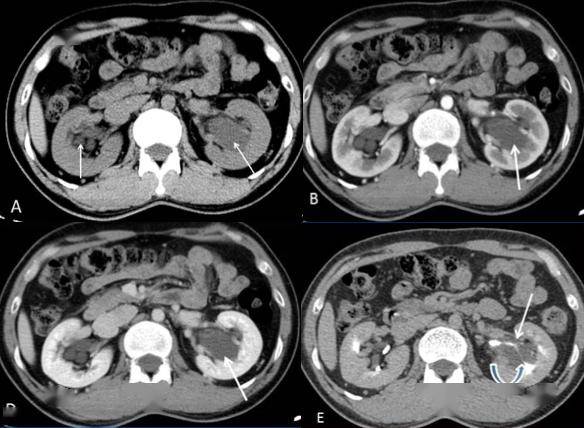

图5 髓质海绵肾典型ct表现b图6 髓质海绵肾结石脱落,形成输尿管结石